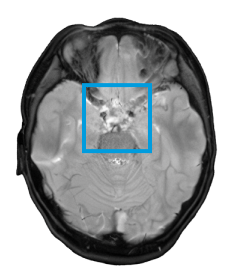

The first and only type II RAF inhibitor for BRAF alterations in relapsed or refractory pediatric low-grade glioma (R/R pLGG)1

OJEMDATM (tovorafenib) is indicated for the treatment of patients 6 months of age and older with relapsed or refractory pediatric low-grade glioma (LGG) harboring a BRAF fusion or rearrangement, or BRAF V600 mutation.